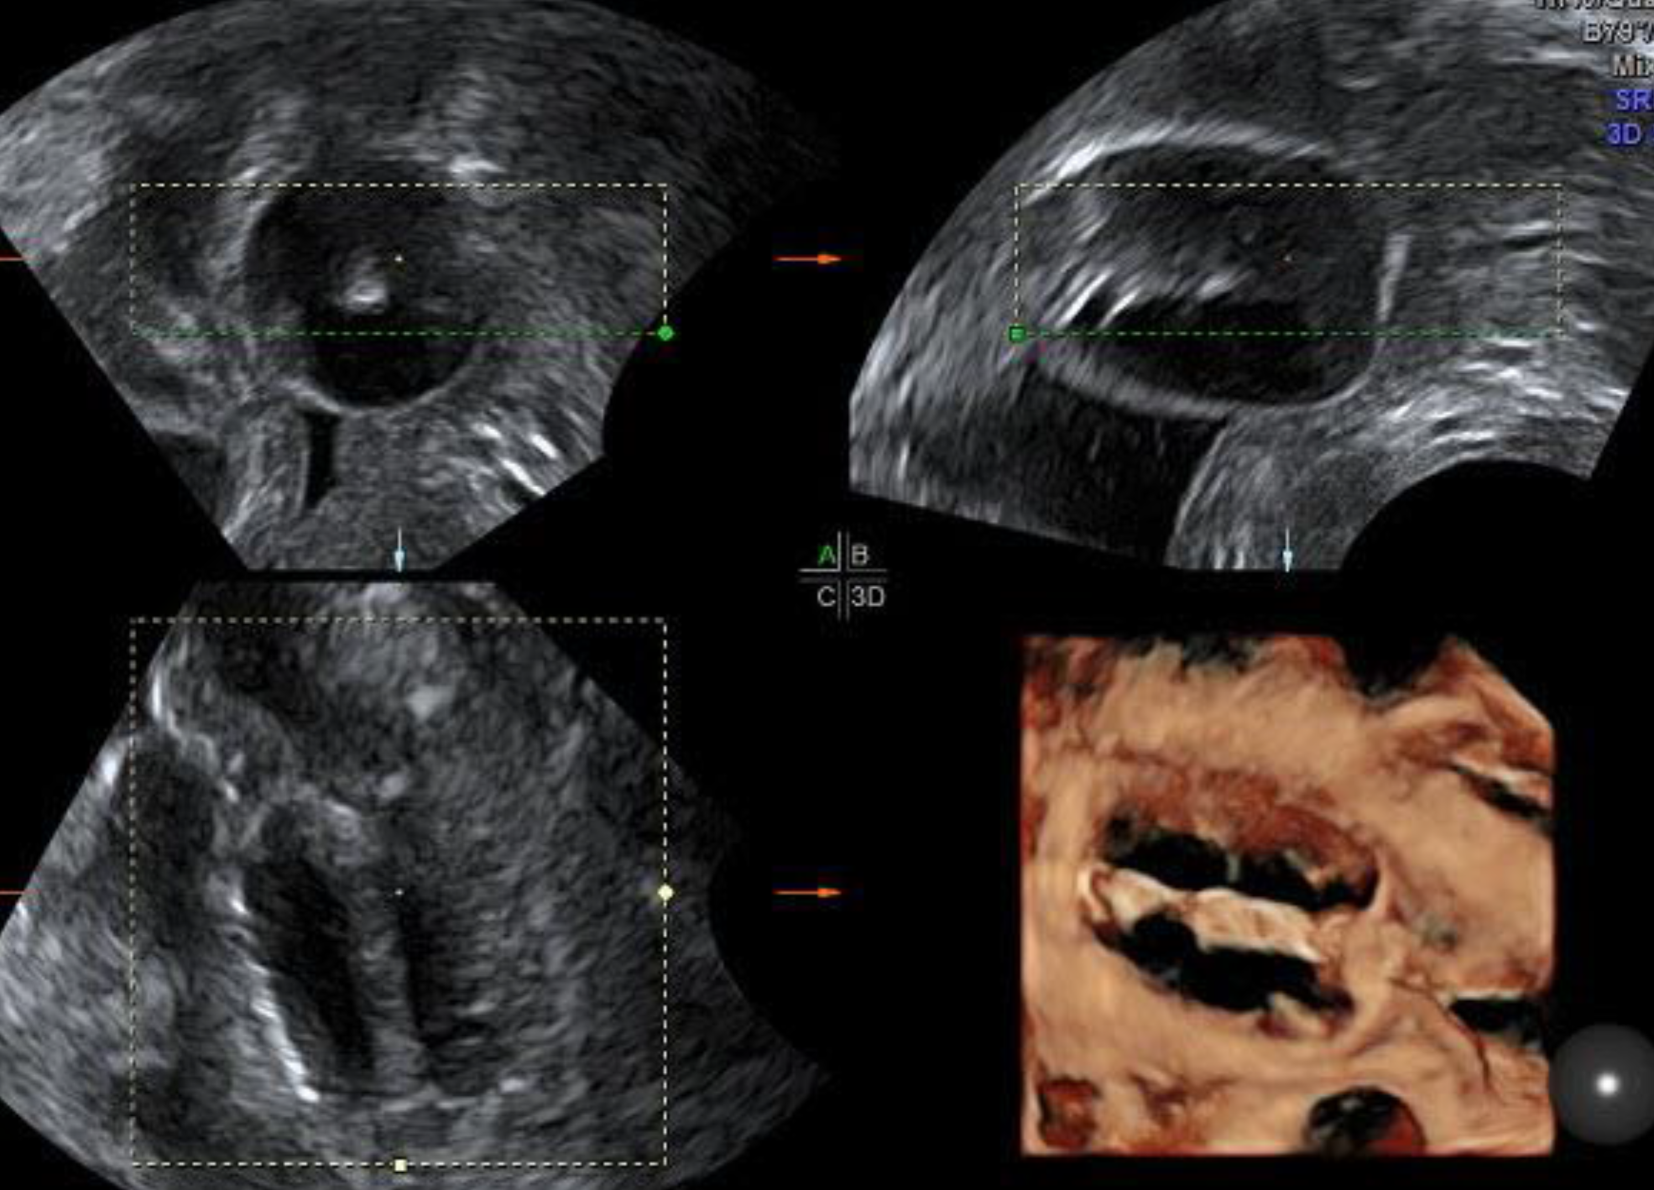

Abb. 3

Beckenniere im Vaginalschall mit zentralem Nierenbecken und Nierenkelchen